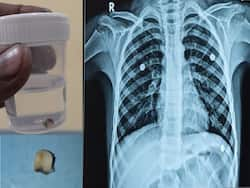

Sharad Pawar Health Update: NCP chief was taken to Ruby Hall Clinic in Pune from Baramati after his health deteriorated, experiencing a cough and difficulty in breathing, his office confirmed.